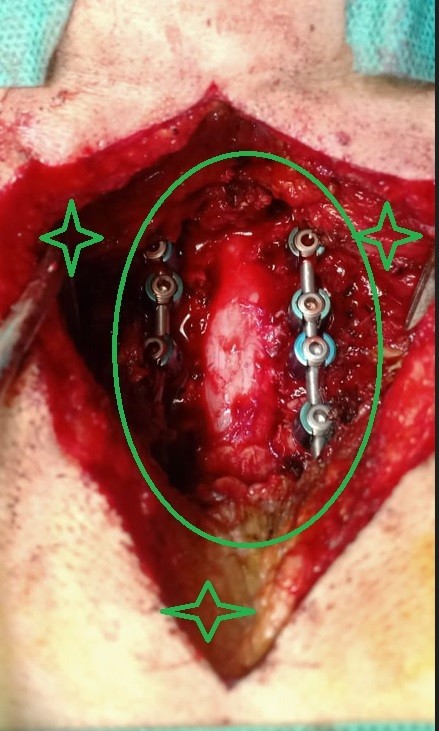

مريض 55 عام يعاني من ضعف بالجانب الأيمن بالجسم وخذل بالأطراف الأربعة مع تيبس اثناء الحركة ناتج عن اصابته بضيق شديد بالفقرات العنقية مع تحدب للأمام بالفقرات العنقية. تم علاجه عن طريق اجراء جراحة لتوسيع مجري القناة العصبية العنقية وتركيب نظام تثبيت خلفي لإصلاح التحدب وتثبيت الفقرات العنقية. كما هو واضح من صور اشعة الرنين قبل الجراحة وصور النخاع بعد رفع الضغط عنه ووضع نظام التثبيت وصور الاشعة المقطعية بعد المتابعة.

تم إجراء جراحة ناجحة للتوسيع الخلفي وتثبيت الفقرات العنقية. هذا الإجراء المتخصص يهدف إلى علاج الضغط على الحبل الشوكي في منطقة الرقبة، والذي ينتج عن تضيق القناة الشوكية أو عدم استقرار الفقرات العنقية.